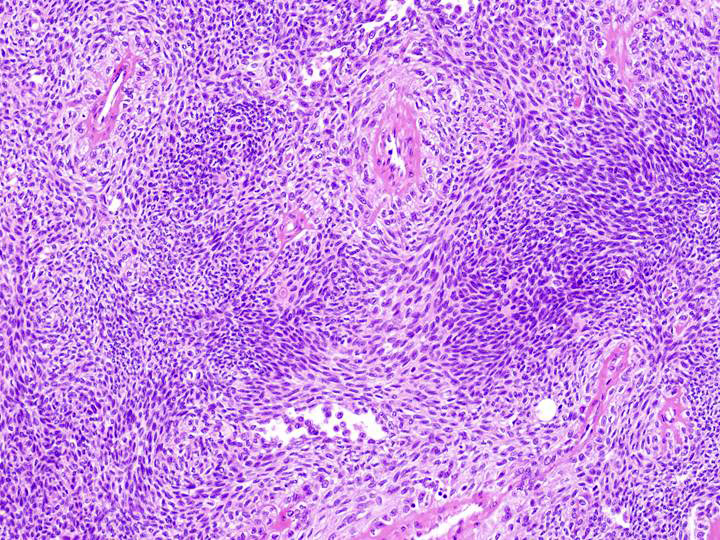

| 腫瘍は淡い好酸性胞体を有する紡錘形細胞および類円形細胞を主体とする. |

一部の結節は腺上皮と明細胞の形態をとる筋上皮よりなり,2層性の配列も認められる. |